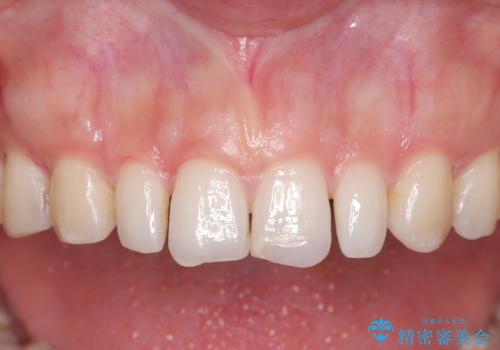

- 歯並びを矯正で整えたあと、上顎左右2番の歯(前歯の横の歯)の「矮小歯(歯が小さい状態)をオールセラミッククラウンで審美修復した症例です。

矯正によって歯並びはきれいに整いましたが、前歯全体のバランスをより自然で美しく仕上げるため、上顎左右2番にオールセラミッククラウンによる審美修復を行いました。

矮小歯はもともと歯が小さいため、削る量を最小限に抑えた負担の少ない治療が可能です。

また、自然な色合いや形になるよう、歯科技工士と連携し、写真を撮影しながら細かく色合わせを行い、周囲の歯になじむよう丁寧に仕上げています。